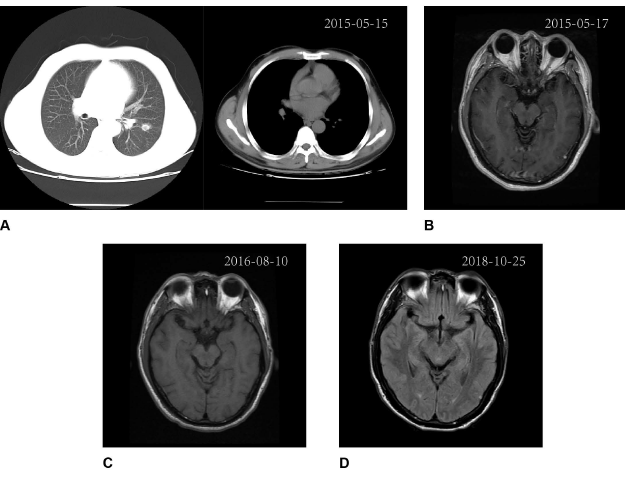

患者,男性,51岁。2015年5月,确诊IA3(T1cN0M0)期肺腺癌(图1 A, B);当月接受胸腔镜左下叶切除术和全身淋巴结清扫术。术后组织送检ARMS-PCR,检出EGFR 19Del。患者未行辅助治疗。

2016年7月,患者出现进行性头痛等疑似进展(PD)的症状,但磁共振成像(MRI)未显示异常(图1 C)。患者接受抗焦虑治疗。

2017年10月-2019年4月,第二次脑脊液NGS检测仍仅检出EGFR 19Del(丰度:27.3%,图2 B)。患者持续使用奥希替尼,病情稳定,癌胚抗原(CEA)水平持续下降(图2 A),症状缓解(KPS评分:90)。根据影像学结果,未观察到疾病进展(图1 D)。

图1. 患者诊疗期间影像学监测结果

A、B:影像学结果表明患者确诊时未发生转移;C:2016年8月10日,MRI检测未发现进展;D:2018年10月25日,影像学检测未发现进展